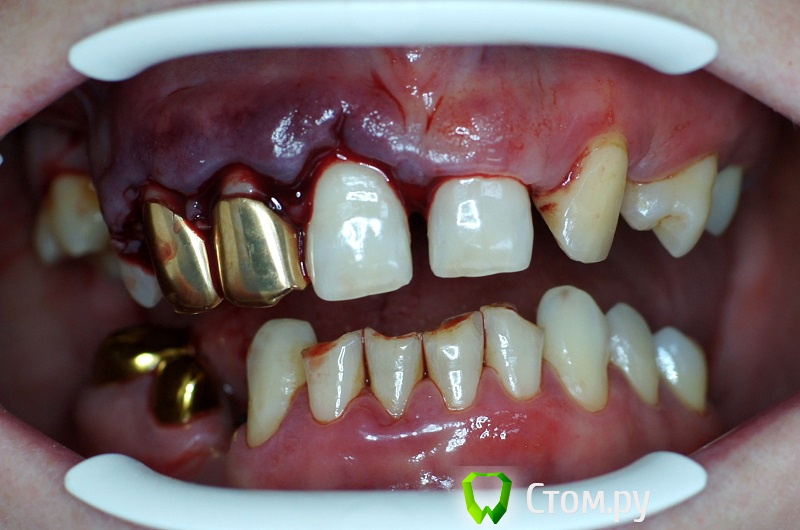

rin3225 Опубликовано 8 октября, 2014 Поделиться Опубликовано 8 октября, 2014 У пациента было желание сделать красивые зубы и улыбку!Проблема заключалась в массивной верхней челюсти , глубоком перекрытии и пациент не мог уйти без зубов! Отлив модели и выставив в центральную окклюзию было понятно, что без удаления всех зубов и поднятия прикуса с данной проблемой вопрос не решится. Обговорив все нюансы с пациентом,и получив согласие, было запланировано. заранее изготовлены акриловые протезы, предложено удаление всех зубов с одномоментной установкой имплантатов, внутриротавая сварка для первичной стабильности имплантатов и немедленная нагрузка 16 Ссылка на комментарий

Дмитрий Никитюк Опубликовано 8 октября, 2014 Поделиться Опубликовано 8 октября, 2014 У пациента было желание сделать красивые зубы и улыбку! Зачем так много имплантатов? Почему проволока приварена в поддесневом пространстве? Каким образом крепятся протезы? Ведь фиксация должна быть винтовая, а каркасс должен располагаться внутри протеза. 1 Ссылка на комментарий

rin3225 Опубликовано 8 октября, 2014 Автор Поделиться Опубликовано 8 октября, 2014 Зачем так много имплантатов?Почему проволока приварена в поддесневом пространстве?Каким образом крепятся протезы? Ведь фиксация должна быть винтовая, а каркасс должен располагаться внутри протеза. Проволку можно преварить как под десной так и над десной, это не каркас протеза, протезы сьемные для соблюдения гигиены.В дольнейшем кострукция будет поменена на несьемные 1 Ссылка на комментарий